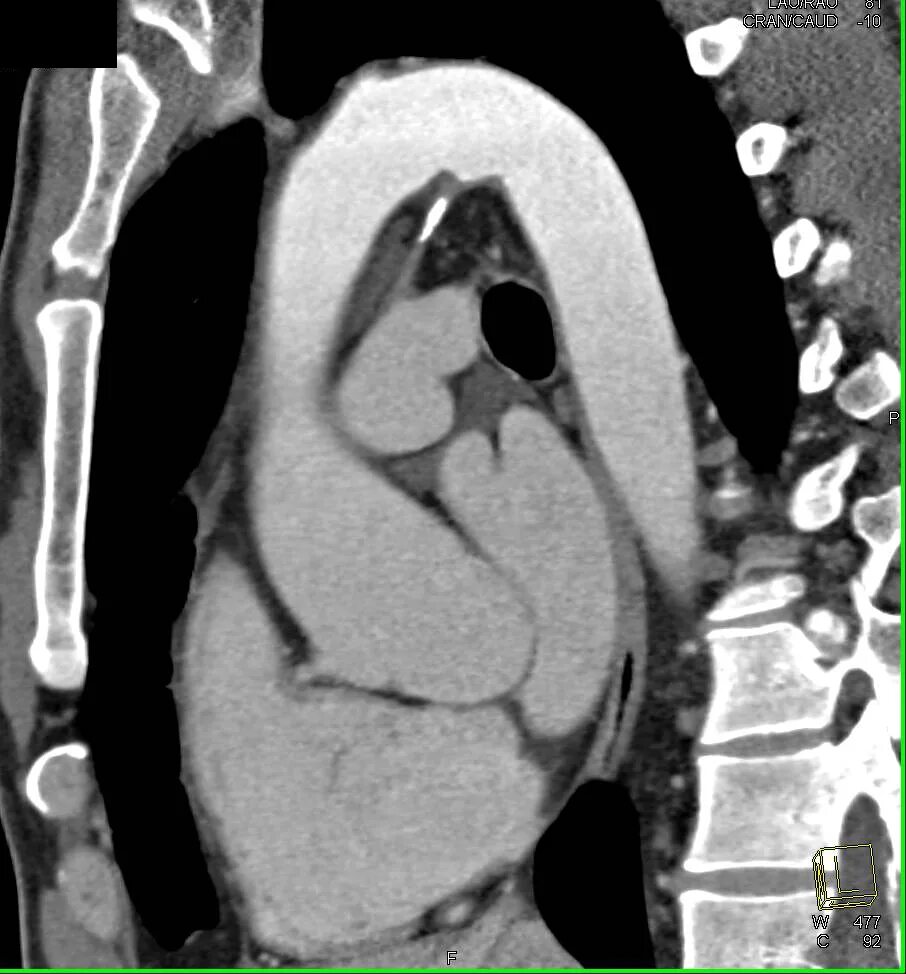

Уплотнение стенок ак